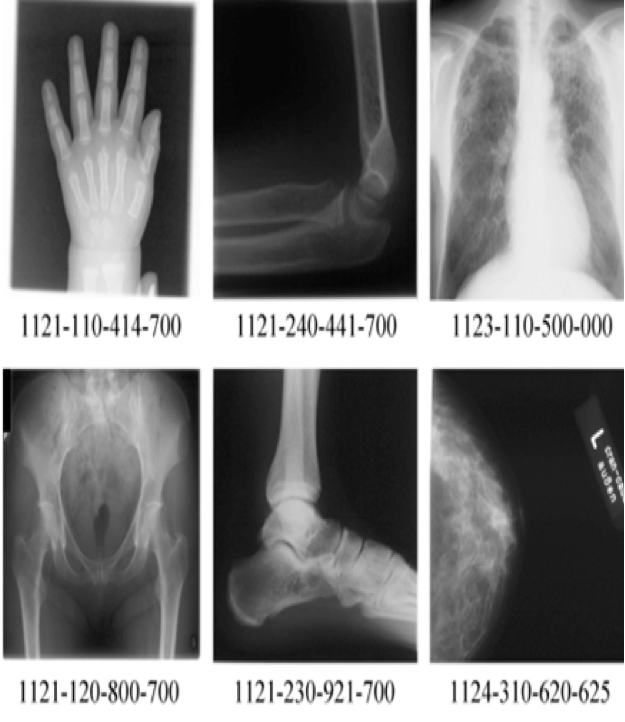

In this paper the image Retrieval in Medical Applications (IRMA) database [25] the benchmark dataset from ImageCLEFmed09, a retrieval challenge in a collection of medical images, is used to validate the proposed method. The IRMA database is a collection of more than 14,000 x-ray images (radiographs) randomly collected from daily routine work which is used for training and testing. All the images were classified in 57 categories and annotated with the IRMA code. The IRMA codes (manually created by several clinicians), which is a string of 13 characters within the set of 0, ,9,a, ,z, contain information on technical, biological and diagnostic traits of the image in a structured manner: TTTT-DDD-AAA-BBB. Figure 2 shows some sample images in the IRMA dataset with their corresponding IRMA code.

Refer to caption

Figure 2: Sample images from IRMA dataset with their IRMA codes.

In this dataset, a total of 12,677 x-ray images is used for training and the remaining 1,733 images are considered as testing data. The distribution of data in training and testing images shows that there exists considerable imbalance in IRMA dataset (Figure 3).